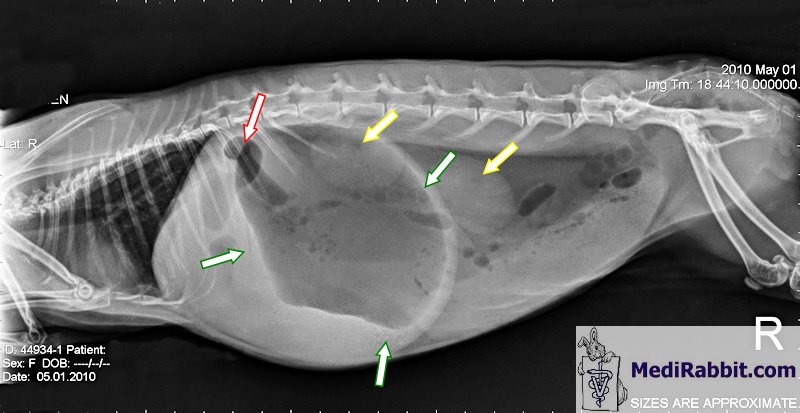

secondairement. Carmela,

sauvée d’un élevage de jardin amateur, avait environ 3 ans quand elle a

développé un météorisme aigu. Les radiographies suivantes ont été prises à

l’hôpital vétérinaire du Gulf Coast, environ 8 heures après que Carmela a été

intubée. Dans les deux radios, il est

possible de voir un estomac extrêmement distendu, qui compresse son cœur, ses

poumons et d’autres organes. Malgré les soins immédiats prodigués par des

vétérinaires compétents, Carmela n’a pas pu être aidée et a été endormie afin

de la soulager de ses douleurs.